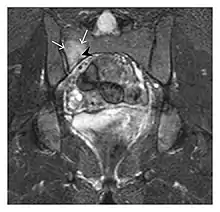

The greater tuberosity of the humerus is also an illustrative location of occult fractures. The osseous injury may follow seizures, glenohumeral dislocation, forced abduction, or direct impaction. They are commonly discovered on MRI in symptomatic patients with suspicion of rotator cuff tear. Coronal images are best suited for detection. They appear as crescentic oblique lines surrounded by a bone marrow edema pattern (Figure 5). The rotator cuff must be inspected since associated ligamentous lesions are common. In the ankle, malleoli and tarsal bones should be checked carefully for any cortical disruptions and radiolucent lines that may reveal a fracture. Awareness of the exact location of the pain will help direct the attention of the interpreter when searching for very subtle signs of fracture (Figure 6).[1]

a

b

Figure 6: Subtle anterior talar fracture in a 39-year-old man presenting with ankle pain after a fall. (a) Anteroposterior radiograph shows a subtle oblique radiolucent line through the talus (white arrows). (b) Sagittal CT reformation confirms the presence of an anterior talar fracture with cortical offset (black arrow). Avulsion fractures, which consist of a detached bone fragment resulting from a ligament or tendon pulling away from the bone, may also present with subtle radiographic signs. Tiny osseous fragments near the presumed attachment site of a ligament suggest this diagnosis. Common sites are the lateral tibial plateau (the Segond fracture), the spinal tuberosity of the tibia resulting from anterior cruciate ligament avulsion, and the ischial tuberosity.[1]